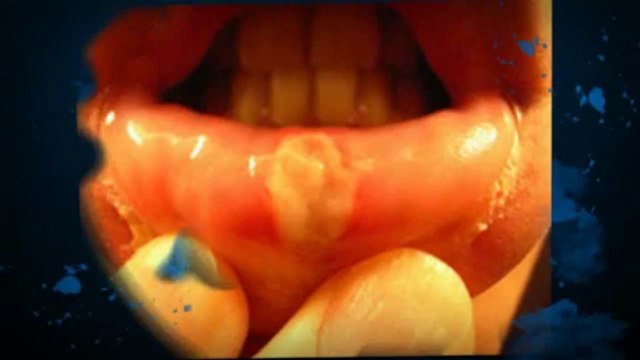

Cold Sores - Natural Ayurvedic Home Remedies